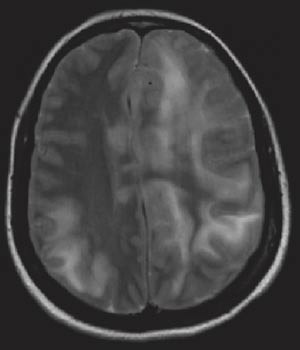

I løpet av første døgn i sykehus utviklet pasienten afasi og økende parese i høyre sides ekstremiteter. Natt til femte døgn i sykehus tilkom redusert bevissthet, og i løpet av noen få timer ble hun komatøs med blodtrykksstigning til 230/130 mm Hg og bradykardi (40 slag per minutt). Hun utviklet venstre oculomotoriusparese som tegn på truende herniering. Cerebral CT viste betydelig ødemutvikling med utslettede sulci over konveksiteten, midtlinjeoverskytning mot høyre og nesten global okklusjon av de basale cisterner (fig 2).